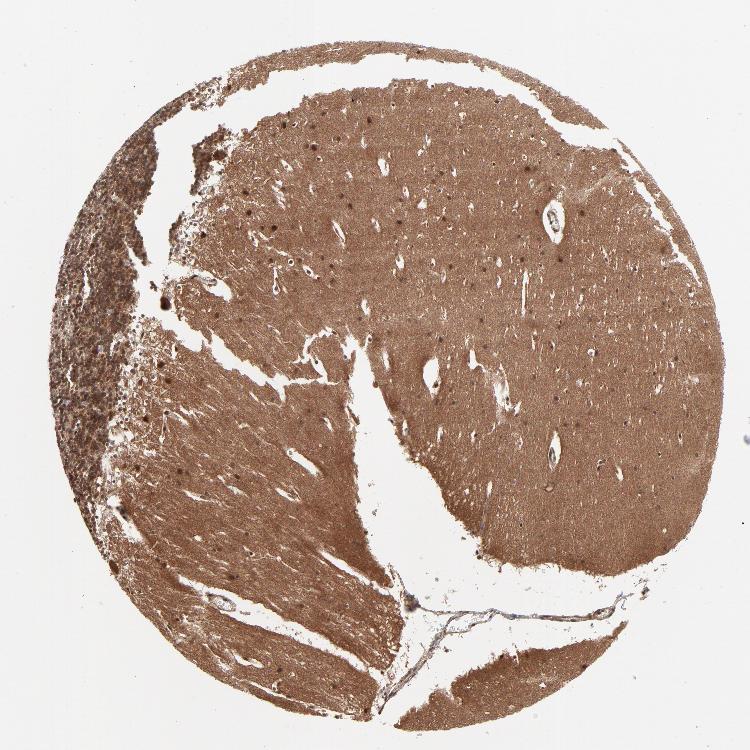

CEREBELLUM - Expression summary

CEREBELLUM - Antibody stainingi

Antibody staining in the annotated cell types in the current human tissue is reported as not detected, low, medium, or high, based on conventional immunohistochemistry profiling in selected tissues. This score is based on the combination of the staining intensity and fraction of stained cells.

Each image is clickable and will lead to virtual microscopy that enables deeper exploration of all samples and also displays staining intensity scores, fraction scores and subcellular localization as well as patient and tissue information for each sample.

Antibody HPA002891Antibody CAB003765Antibody CAB080436

Purkinje cells LowHighHigh

Cells in granular layer HighMediumNot detected

Cells in molecular layer HighLowLow